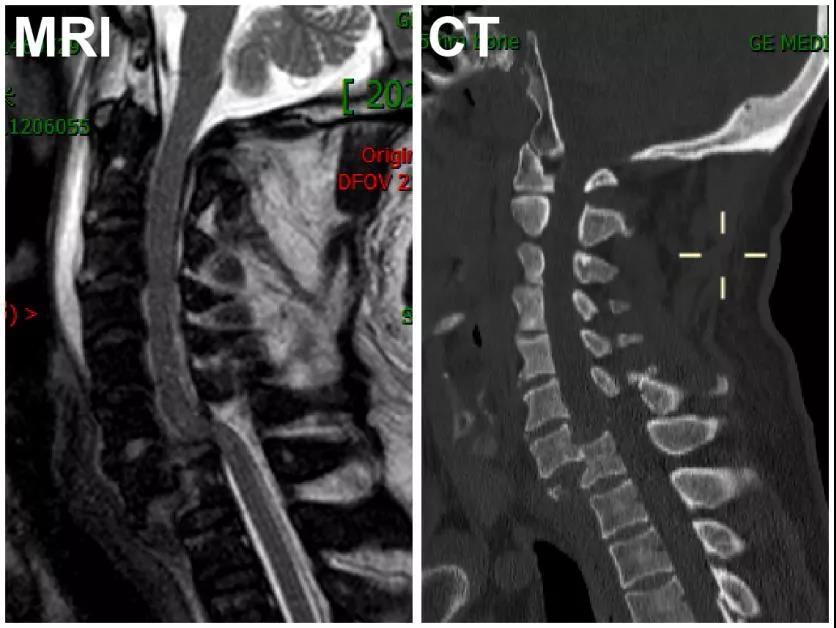

图1、患者入院时的MRI及CT检查显示:C7椎体完全脱位,相应节段脊髓未见明显卡压

影像学的进一步检查显示患者C7椎体完全脱位,其后缘移位至胸椎椎体(T1)前方并形成绞索,但脊髓却未见明显卡压(如图1所示)。这给医生们带来了难题:如何在有效复位固定的同时避免脊髓的二次损伤?